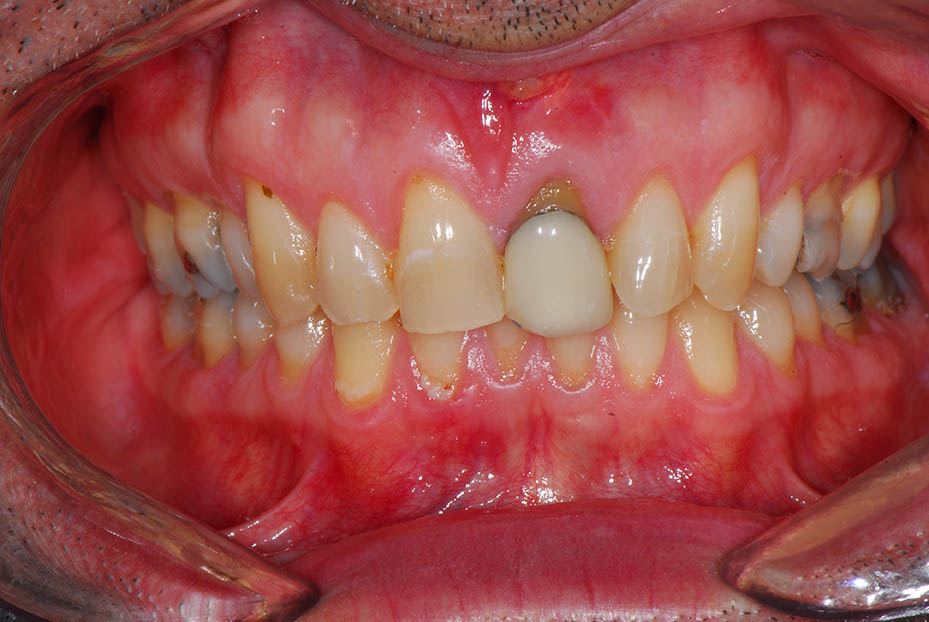

Replacement of badly infected upper left central incisor with a single implant crown.

Before